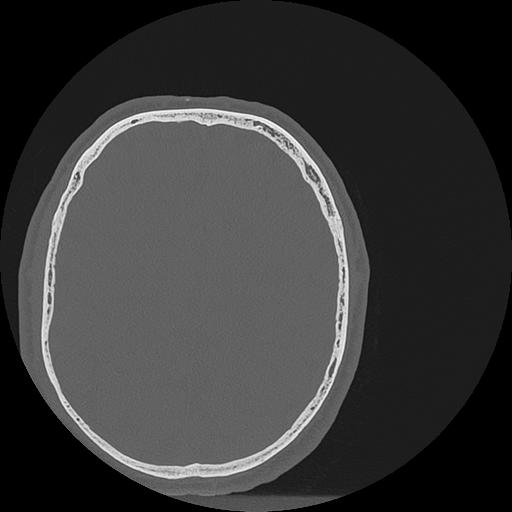

7 HUESO,,Vol,0.5,HUESO,,